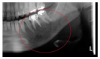

When the patient returned to the clinic 5 months later, additional radiographs were taken and interpreted by an oral pathologist revealing a “moth-eaten” radiolucent lesion of apical resorption around tooth No. 18 (Figure 3 and Figure 4). The area was swollen and teeth Nos. 18 and 19 were tender to percussion. Further testing included a pulp vitality test to tooth No. 18 with a biopsy to the surrounding bone. A cone beam computed tomography scan was also recommended to rule out metastatic disease and intraosseous malignancy. Original differential diagnoses included acute apical abscess and subacute osteomyelitis but after a biopsy the differential diagnoses expanded to myofibroma, lipoma, adenoma, adenocarcinoma, lymphoma and sarcoma. Ultimately, the lesion was described as a malignant spindle tumor compatible with myofibroblastic sarcoma. The patient was referred to a local hospital for treatment, which included surgery to remove the mass, affected tissues, and all portions of diseased bone within the left side of mandible. However, the patient lived for approximately 1 year after surgery, dying 19 months after the onset of chin numbness.

Fig 3. Periapical taken 5 months after Figure 1. Moth-eaten borders and apical root resorption affecting and surrounding tooth No. 18.

Figure 3

Fig 4. An enlarged section of the presurgical panoramic radiograph, taken 5 months after initial complaints of numbness. Affected area noted in red circle.

Figure 4